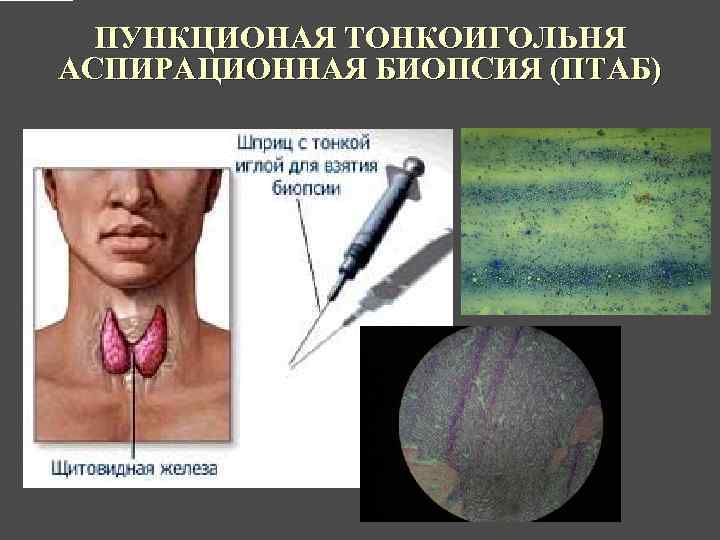

ПУНКЦИОНАЯ ТОНКОИГОЛЬНЯ АСПИРАЦИОННАЯ БИОПСИЯ (ПТАБ)

ПУНКЦИОНАЯ ТОНКОИГОЛЬНЯ АСПИРАЦИОННАЯ БИОПСИЯ (ПТАБ)

ИНТЕРПРЕТАЦИЯ РЕЗУЛЬТАТОВ ПТАБ ► Доброкачественный узел ► Рак ► Узел подозрительный на рак ► Воспалительной процесс ► Материал неинформативен